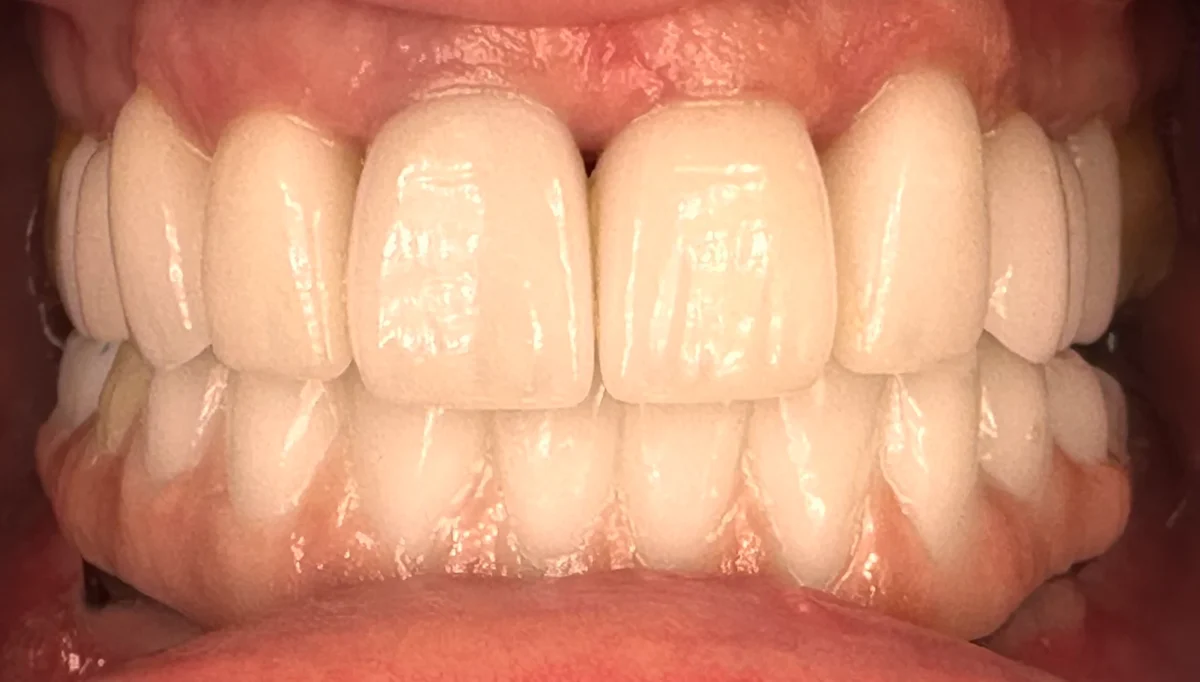

After healing, we designed and delivered her final monolithic zirconia prosthesis for strength, longevity, and a beautiful, bright result.

Final Result

The transformation speaks for itself.

Her final shade choice?

A bold bleach white, reflecting the new chapter she envisioned — and it looks stunning.